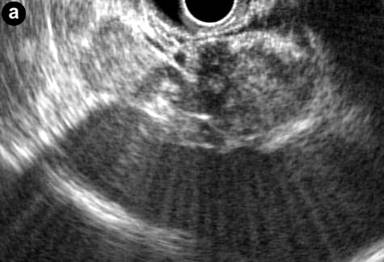

A 53-year-old man was incidentally found to have a cystic tumor in the tail of the pancreas after undergoing an abdominal ultrasound (US), which showed a 41x33 mm cystic mass in the pancreatic tail. He had no abdominal symptoms. The tumor markers, including DUPAN 2, and carbohydrate antigen 19-9, were within the normal ranges. The patient was referred to our hospital for further investigations. A contrast-enhanced CT scan (Figure 1) showed a non-enhanced cyst between the spleen and the pancreas with no solid component. Magnetic resonance cholangiopancreatography (Figure 2) revealed that the main pancreatic duct was regular and had no dilatation, and there was no communication between the cyst and the pancreatic duct. Magnetic resonance imaging (MRI) showed a lesion with a slightly high signal on a T1-weighted image; the lesion, which was well circumscribed, was in the tail of the pancreas (Figure 3). MRI on a T2-weighted image also showed the lesion with a high signal. The cystic tumor was negatively visualized on the PET image. Endoscopic ultrasound (EUS) was performed, which showed a 55x31 mm pancreatic tail lesion with a solid and cystic mixed component (Figure 4a). An endoscopic ultrasound-guided fine-needle aspiration biopsy in a trans-gastric approach of this lesion suggested a diagnosis of a benign squamous cyst (Figure 4b).

Figure 4. a. Endoscopic ultrasound was performed, which showed a 55x21 mm pancreatic tail lesion with solid and cystic mixed component. b. Endoscopic ultrasound-guided fine-needle aspiration biopsy in a transgastric approach of this lesion. |